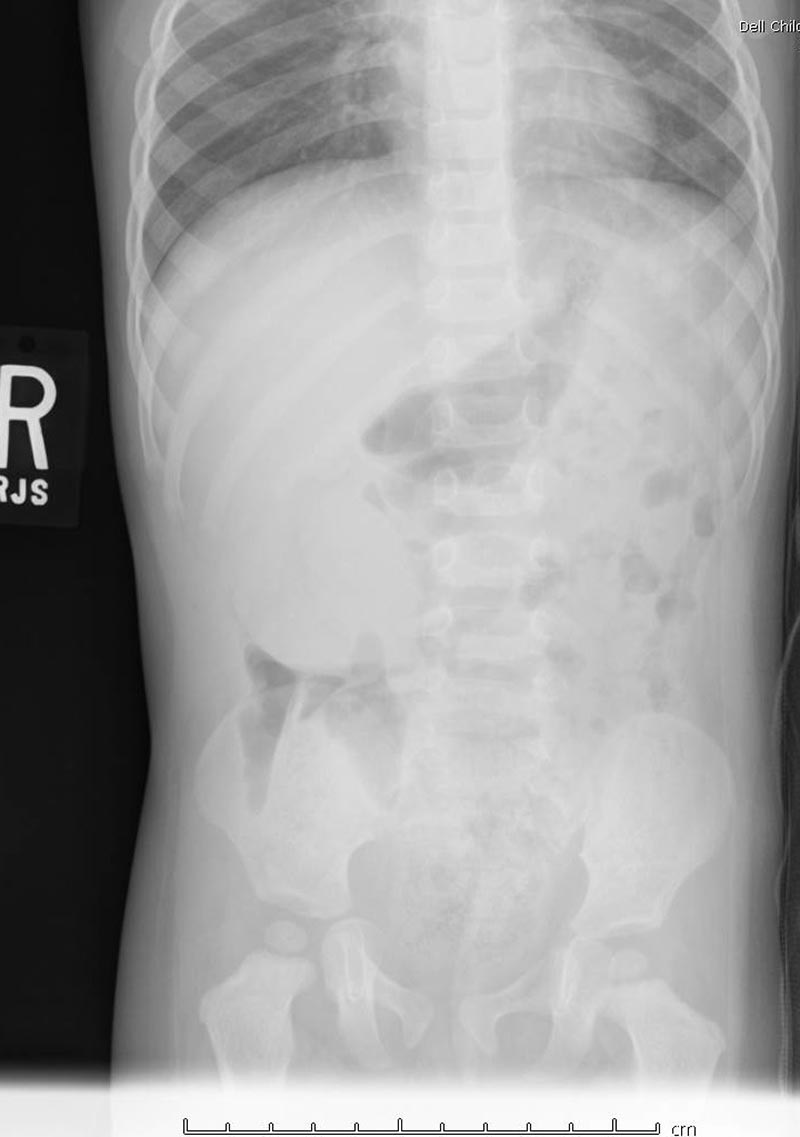

10-month-old male infant presents to the ED by EMS with vomiting and altered mental status (AMS). Infant arrives to the ED awake but poorly interactive. Ultimately, the infant will be diagnosed with intussusception and hypovolemic shock based on the history, physical exam and ultrasound findings. Learners are expected to establish a differential diagnosis of AMS appropriate for an infant, demonstrate appropriate resuscitative interventions, and use appropriate imaging and labs to help identify the cause of AMS.